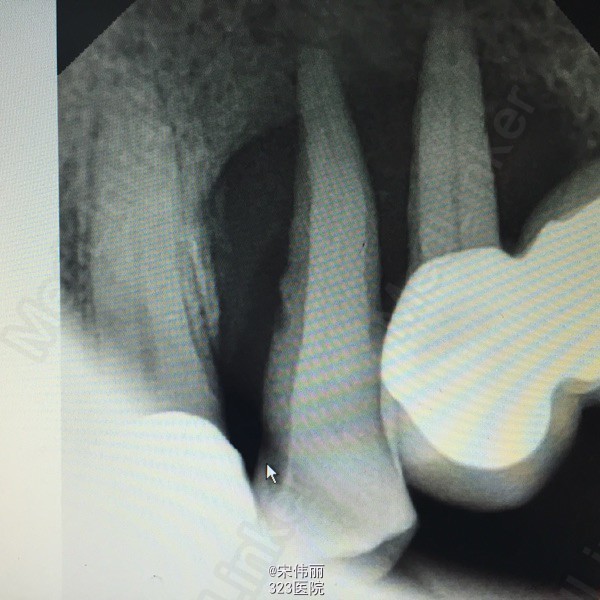

25、26、27冠修复,松动3度,24松动3度,龈袋探深7mm左右,12残根,14、15、16冠修复,下颌重度磨耗 x线示:24、25牙槽骨吸收至根尖

诊断:24、25重度牙周炎 建议:24、25、26、27拔除 处理:全身状况稳定,24、25、26、27“必”麻下顺利拔除,搔刮牙槽窝,牙槽窝复位,缝合4针,咬干棉球止血。